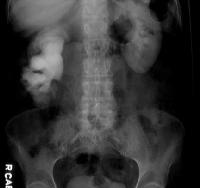

Investigation

Medical history by the patient and clinical examination by the doctor helps in diagnosis. Blood test is done. Ultrasound of the bladder and kidneys is recommended. IVP is recommended. Renal scan is advised. Abdominal CT scan may be required. Uroflowmetry, urodynamic studies are done.